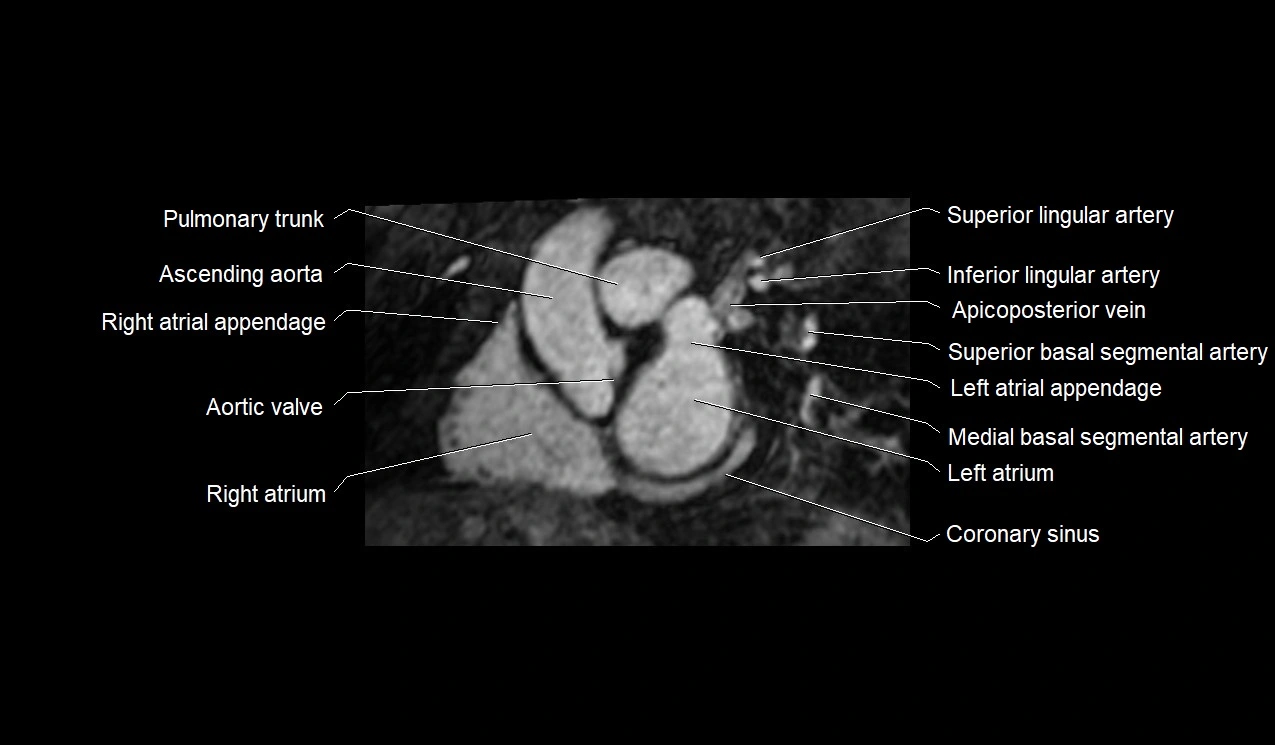

MRI image